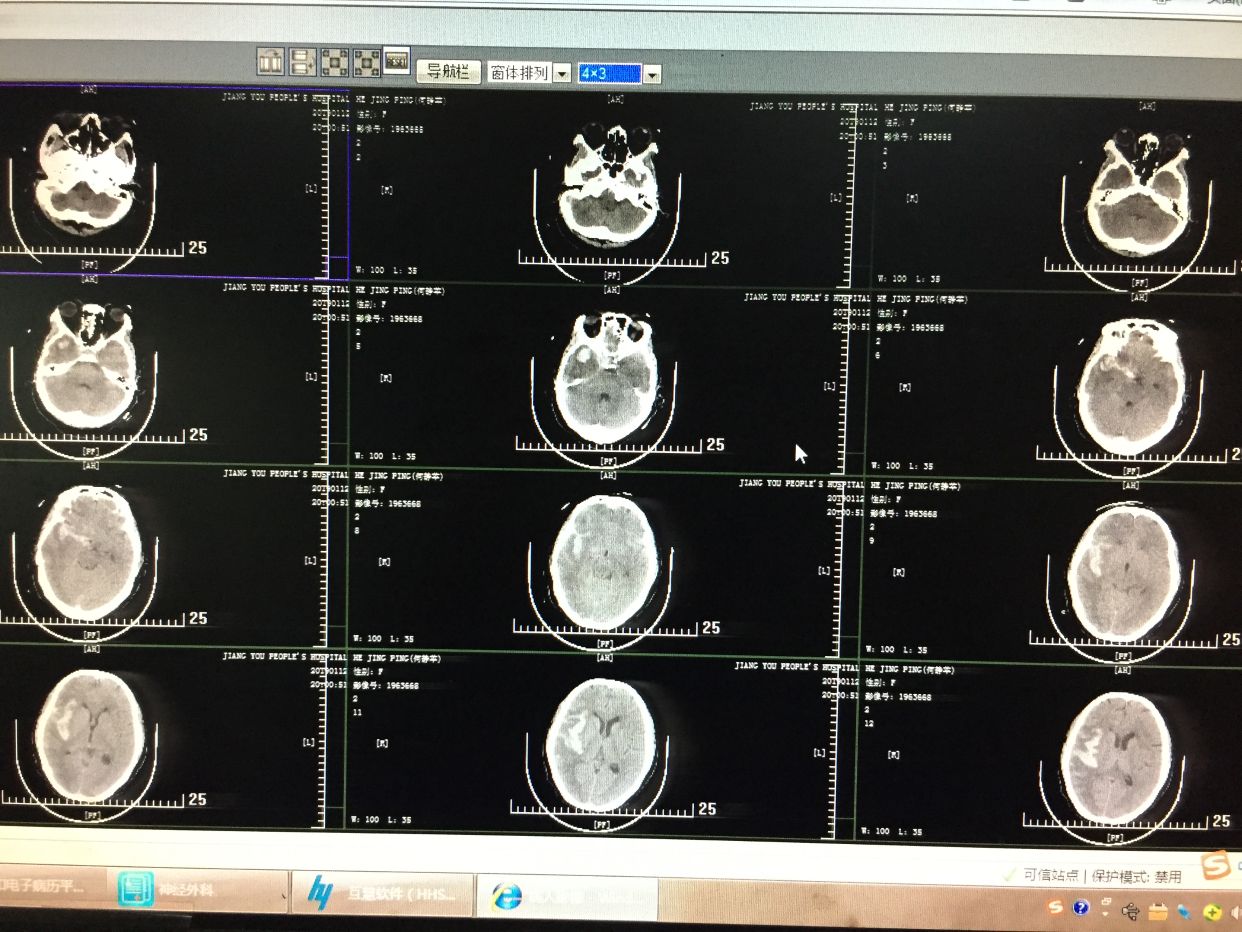

65岁女性,两次破裂出血,运气很好,术前还是清醒的

CTA示右侧大脑中分叉部动脉瘤,瘤子小,颈宽,主要累及下干,颈内动脉预期